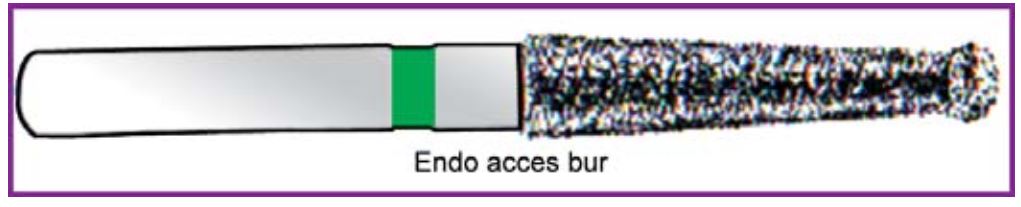

Các mũi khoan cần thiết cho mở tủy ngoài bộ dụng cụ cơ bản:

Khi đã có cảm giác hẫng tay thì chứng tỏ phần trần tủy đã thủng, nên sử dụng các mũi khoan có đầu tận cùng an toàn để tiếp tục (H5.4).